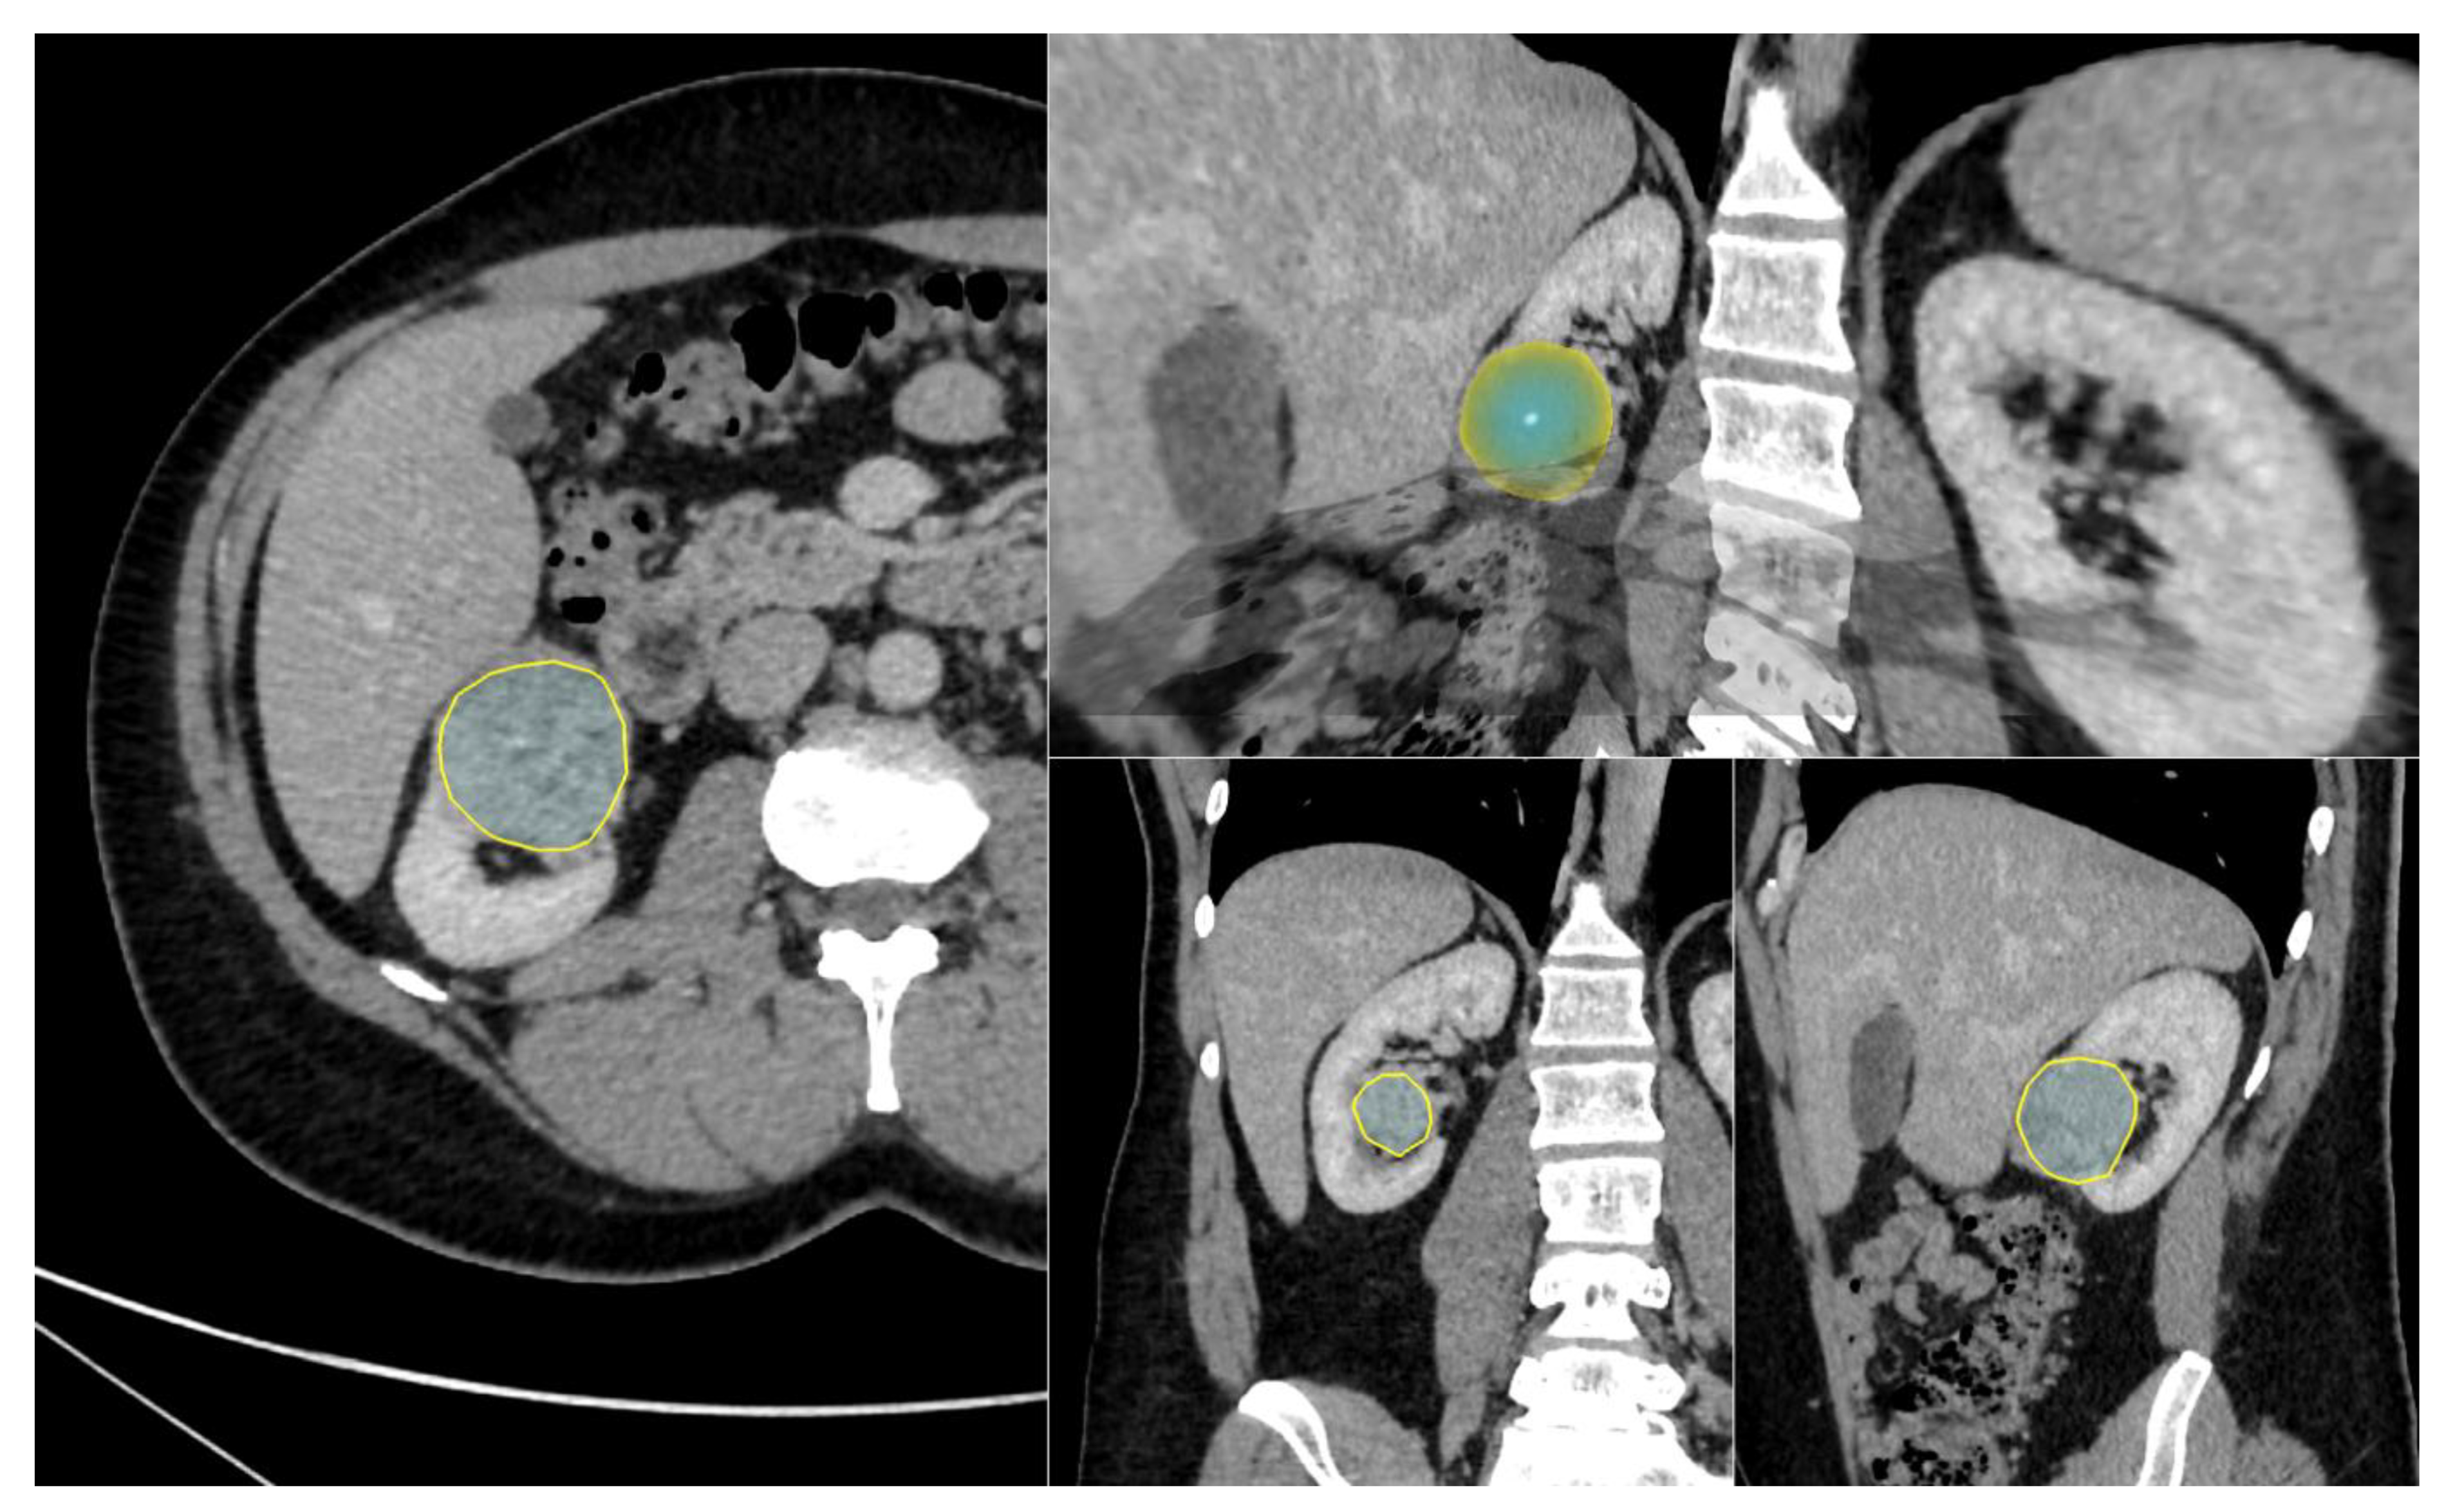

2.2. CT Examinations

2.3. CT

3.3. Three-Dimensional Radiomic Features